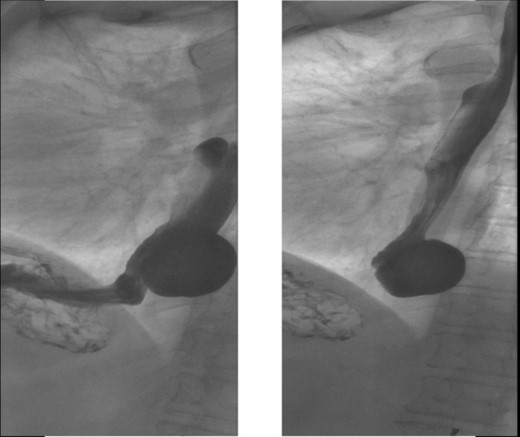

A 72-year-old woman with a past medical history of coronary artery disease and chronic gastroesophageal reflux disease (GERD) with hiatal hernia status postsurgical correction by Nissen’s fundoplication 20 years ago, presented with worsening episodes of intermittent dysphagia, heartburn, and postprandial cough of ~2 years duration but worsening symptoms over the past 2 months. She denies any symptoms of food regurgitation, nausea, vomiting, appetite, or weight changes. Upon her initial clinic evaluation, she had normal vital signs and unremarkable findings on the physical exam. The decision was made to start her empirically on a proton pump inhibitor, assuming her symptoms are related to GERD, to which she did not respond appropriately. A subsequent upper endoscopy revealed a large epiphrenic wide-mouthed ED (Fig. 1). Additionally, an esophagram showed a 6.0 × 5.0 cm epiphrenic ED with a 3.3 cm neck (Fig. 2). High-resolution esophageal manometry (HREM) was performed; thereafter, revealing a normal motility pattern (Fig. 3). She was then referred to cardiothoracic surgery for consideration of surgical repair. She was initially advised to follow a dysphagia-specific diet and wait conservatively on her symptoms, but no changes were observed in her clinical course over 6 months. The patient subsequently underwent a successful uncomplicated esophageal diverticulectomy with myotomy, conducted through a lateral thoracotomy. During surgery, an esophagogastroduodenoscopy (EGD) revealed an ED at 35 cm in the gastroesophageal (GE) junction at 40 cm in the epiphrenic region. A standard posterior lateral thoracotomy was performed in the serratus-sparing fashion, and the pleural space was entered at the seventh intercostal space. The esophagus was encircled with a Penrose drain lifting it up, and it was freed from the periaortic tissue, and the ED cleared off all muscle fibers. The diverticulum was excised from the esophagus using a purple load stapler with an EGD scope in place to prevent esophageal narrowing. A myotomy was performed from the GE junction proximally, with negative leak testing. The muscle layer was then imbricated over the area of diverticulectomy, and a chest tube was inserted for drainage. A postoperative esophagram confirmed no presence of an ED (Fig. 4). Immediately after the surgery, the patient had a complete resolution of her symptoms, and during her 1-year follow-up visit, she remained asymptomatic.

X-ray esophagram fluoroscopy showing a 6.0 × 5.0 cm epiphrenic ED with a 3.3 cm neck.